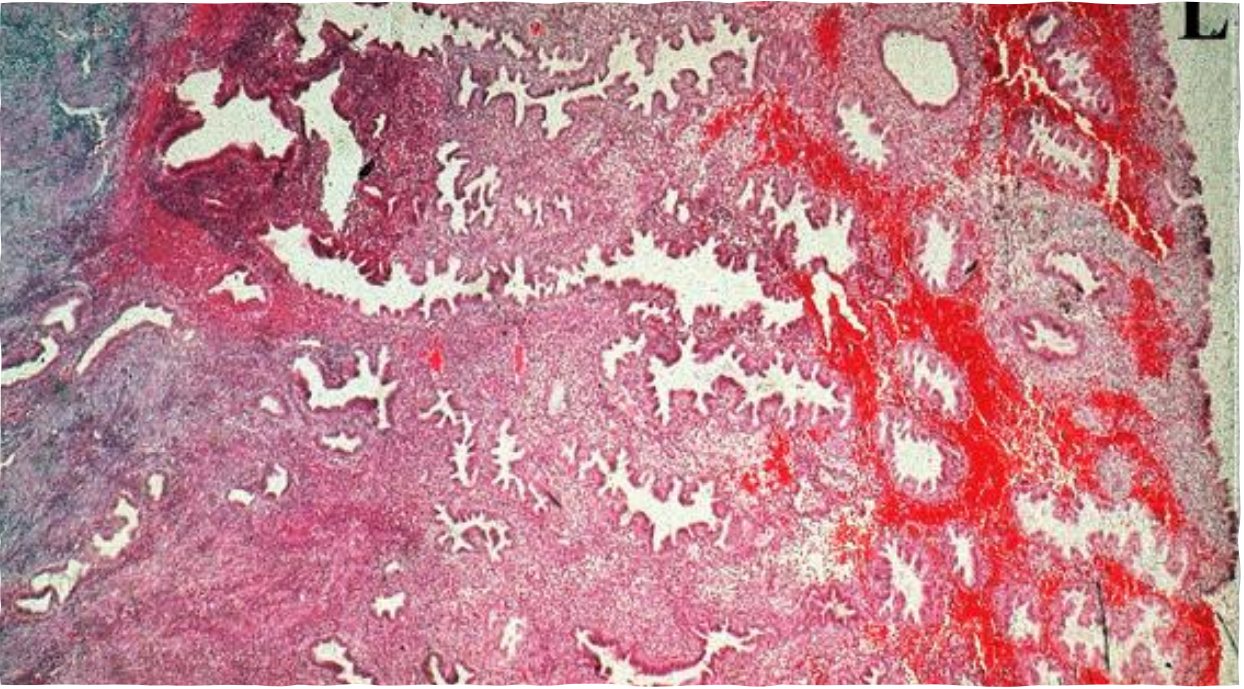

Graffian follicle